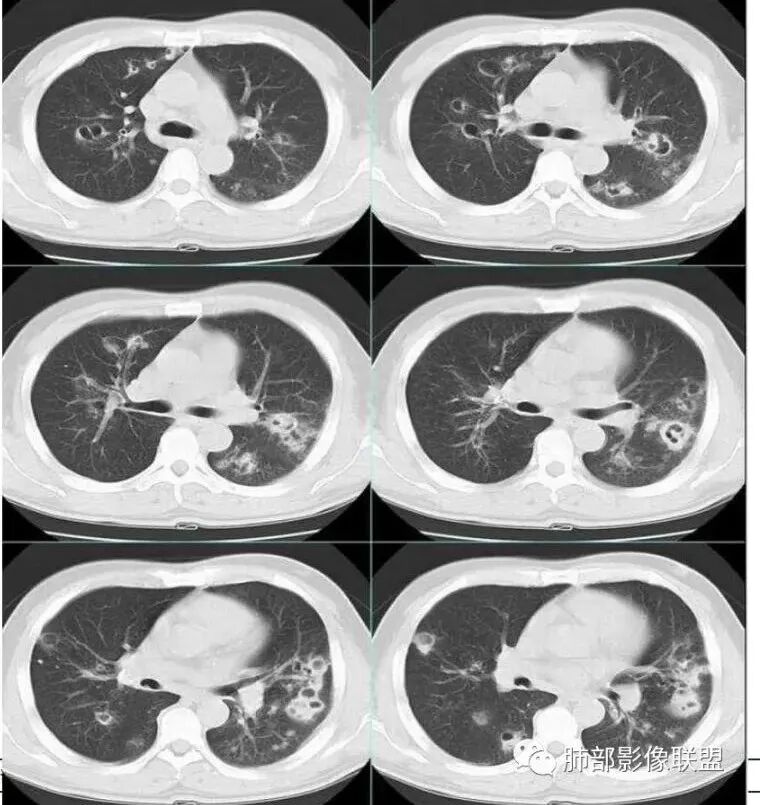

治疗后复查

今天的病例复查很符合金葡菌

第一次不典型

左下肺的囊腔呈簇状分布

这个区域应该是外侧最重的,但是没有看到空洞。二元论也可以,单纯从影像看金葡也不一定都是小叶性改变的,肺泡性改变也可以,从病史看,可能病毒合并金葡。

金葡不会等到半个月还是斑片状影的,金葡变化很快,一般是按天、甚至按小时计算的。

这个炎症当时也考虑过金葡,但是病史是半个月,所以就排除了,病史不符合金葡

这个病史发热三天,胸痛可能是后面金葡引起的,这些不一定是金葡,可能就有基础疾病,合并的这个。真正的病史就是金葡引起,病史就发热三天,近期加重,这三天就是金葡的改变。

就是说这个基础病变不知道是什么,肯定有基础病变,不然不符合,因为前上个星期才去讲这个金葡的,当时一看,这个斑片斑片确实有金葡的一些特点存在,支气管壁有增厚。

金黄色葡萄球菌为厌氧的革兰氏阳性球菌,可产生凝固酶和多种其他毒素及酶,其感染的病理改变中最突出的特点是化脓倾向强,尤其是MRSA肺炎具有起病急,病情进展快,病死率高的特点,早期诊断并进行足量、敏感的抗菌药物治疗对减少其发病率及死亡率具有重要作用。金葡菌肺炎常表现为多种CT征象并存,磨玻璃密度影及斑片影是最常见、最主要的CT表现,肺气囊是典型的影像表现。肺气囊是支气管周围脓肿使终末细支气管和肺泡发生坏死,当与支气管相通后坏死物质排空形成的含气空腔,表现为圆形或类圆形的薄壁空腔,壁厚1—2 mm。部分患者因起病急,使用抗生素较早,在一定程度上也影响了金葡菌感染的程度及转归,表现为磨玻璃样影及斑片影,因此在脓肿基础上形成的肺气囊亦相对较少或出现较晚。